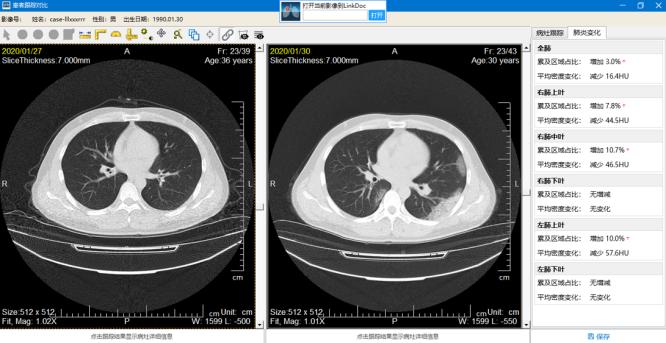

“從肺炎病變識別,到肺炎病變分析(累及區(qū)域面積、實(shí)變占比等),再到病情進(jìn)展評估等,新冠肺炎AI輔診系統(tǒng)都可以輔助醫(yī)生。能夠幫助臨床專家快速定位病灶,更準(zhǔn)確地幫助專家確定病情進(jìn)展,并根據(jù)檢測及分析結(jié)果生成輔助報(bào)告?!敝x穎夫表示,尤其對于一些危重癥患者的評估、治療,年輕醫(yī)生會感覺十分棘手,而“新冠肺炎AI輔診系統(tǒng)”就有了更大的施展空間。

據(jù)悉,該系統(tǒng)可以通過對異常病例的分析學(xué)習(xí),建立人工智能風(fēng)險(xiǎn)預(yù)測模型,對風(fēng)險(xiǎn)較高的患者進(jìn)行預(yù)警提示,為重?;颊吒皶r(shí)地提供有效的醫(yī)療服務(wù)。在治療方案的推進(jìn)過程中,人工智能技術(shù)可以自動追蹤對比患者多次的CT,自動分析患者的病情進(jìn)展情況。